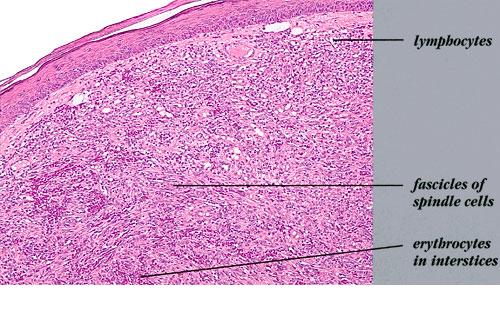

Nodular lesions consist predominantly of spindle cells arranged in bundles and interlacing fascicles and interspersed, irregular, slit-like vascular spaces without endothelial linings. Advanced lesions may display pronounced pleomorphism, nuclear atypia, and mitotic figures. At the periphery of solid tumors, (lymph) angiomatous-like portions of KS with bizarre vascular lumina and intravascular and extravasated erythrocytes, as well as siderophages, may be preserved. Erythrocytes, which appear as eosinophilic globules, are trapped within the slits and clefts formed by the spindle cells and erythrophagocytosis are occasionally observed. As in all other stages of KS, a moderate inflammatory infiltrate consisting of lymphocytes, histiocytes, plasma cells, and, sporadically, neutrophils is regularly present.